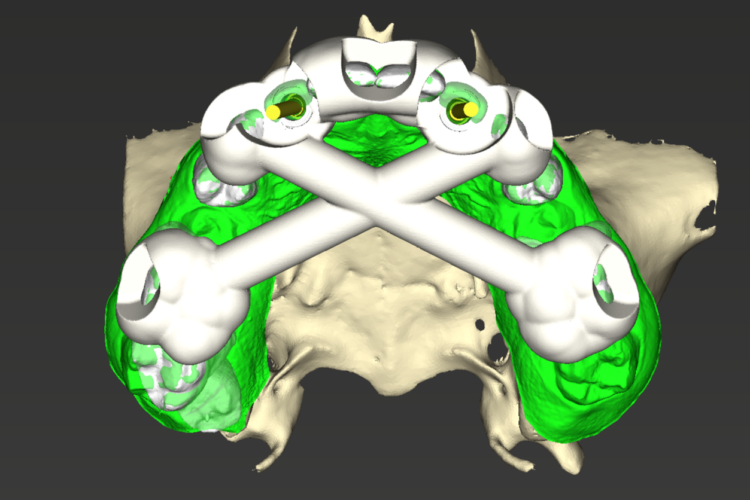

After completing orthodontic treatment, the patient attended a workup appointment, which included a CT scan, intraoral scans and pre-surgical photos and measurements.

The implant surgery was performed in May 2023 and was filmed live as part of a surgical demonstration for the delegates on a guided surgery course being run by the Fitz Fahey Academy. Implants were placed in the UR2 and UL2 spaces with simultaneous hard and soft tissue grafting. Following the surgery, the patient was provided temporary teeth and instructed to avoid putting undue pressure on the implants during healing.